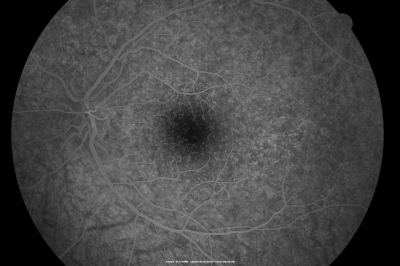

Basal Laminar Drusen - Cuticular Drusen - 19 Year Old with Lupus Nephritis

19-year-old.  She has a history of developing severe systemic lupus erythematosus in 2001.  She was in renal failure and had biopsy proven Class 2 lupus nephritis.  She is currently on Plaquenil 400 mg for six years, as well as Prednisolone orally, every other day. OD 20/20, OS 20/25.